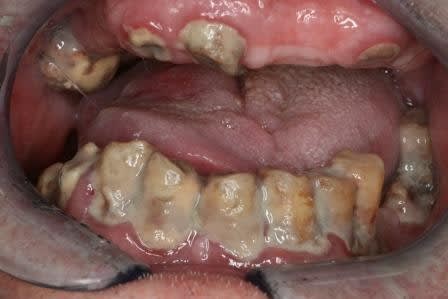

Voilà les confrères Allemands m´ont envoyé quelques photos.... nous avons aussi des champions ici!!! :-)

3 la58kb - Eugenol

4 otfo0a - Eugenol

2 hgapkf - Eugenol

j´ai oublié une...mon favori!

1 tbz0h3 - Eugenol